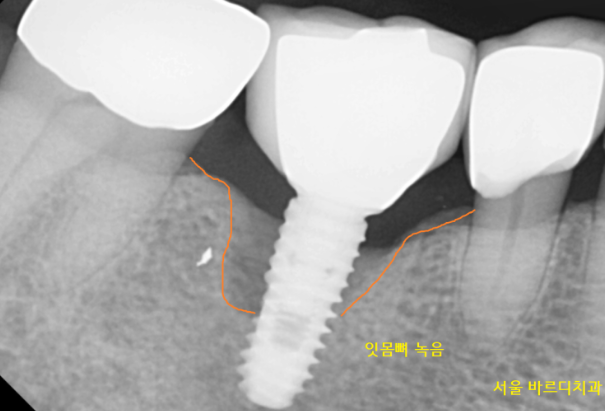

기존에 타 병원에서 식립했던 임플란트를 제거 후

재수술

그러니까 임플란트 교체하기로 상담해 드렸습니다.

기존에 문제를 일으킨 임플란트를 제거 후

새로운 제품으로 교체

녹은 잇몸 뼈는 뼈이식을 통해 해결했습니다.

230406

임플란트 교체 후 2개월 뒤 체크

230613

수술 후 4개월이 지나

보철을 새로 만드는 작업을 진행했습니다.

230116~230613

수술 전후 녹았던 잇몸뼈가

임플란트 쪽까지 채워진 거 보이시죠~??

이제 흔들림도 없고

잇몸 붓고 피가나는 증상도 없어지실겁니다.